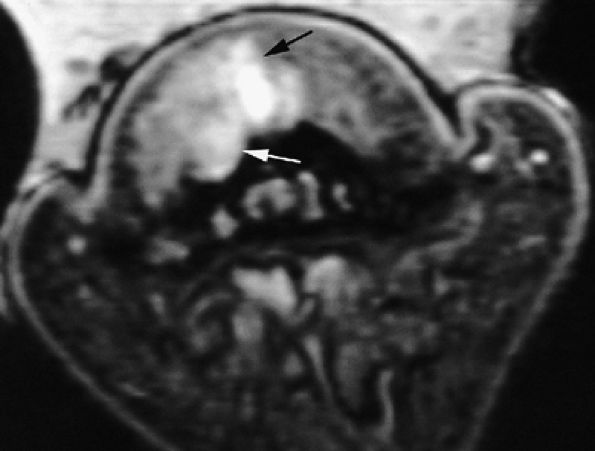

The UCL lies deep to the overlying low-signal adductor aponeurosis on coronal images (Figs. 11.7 and Fig. 11.8). In a nondisplaced partial or complete tear of the UCL, the ligament appears thickened all along its course, sometimes with a small gap. When displaced, the UCL appears as a proximally retracted round or stump-like structure, which demonstrates low signal on all sequences. It is no longer parallel to the long axis of the thumb and presents an increased horizontal orientation.

Stener's lesion may present with a “yo-yo on a string” pattern, with the retracted and balled-up UCL representing the yo-yo and the more distal linear adductor aponeurosis representing the string (Fig. 11.9).

On axial images, the ligament may be seen lying above or intersecting the adductor aponeurosis.

FIGURE 11.7 ● Coronal post-contrast T1-weighted image showing a nondisplaced tear of the UCL of the first metacarpophalangeal joint (MP) joint. The torn UCL is elongated beneath the adductor aponeurosis (AA). There is focal enhancement of the tear (asterisk). 1 MC, first metacarpal.

FIGURE 11.8 ● MR arthrography of nondisplaced tear of the UCL of the first MP joint. Coronal (A) and sagittal multiplanar reformatted (MPR) (B) T1-weighted fat-suppressed 3D gradient-echo images showing an oblique tear (asterisk) of the UCL without avulsion. Thearrows mark the distal (black) and proximal (white) aspects of the torn UCL. The sagittal MPR slice is defined along the course of the UCL. MC, metacarpal; AA, adductor aponeurosis.